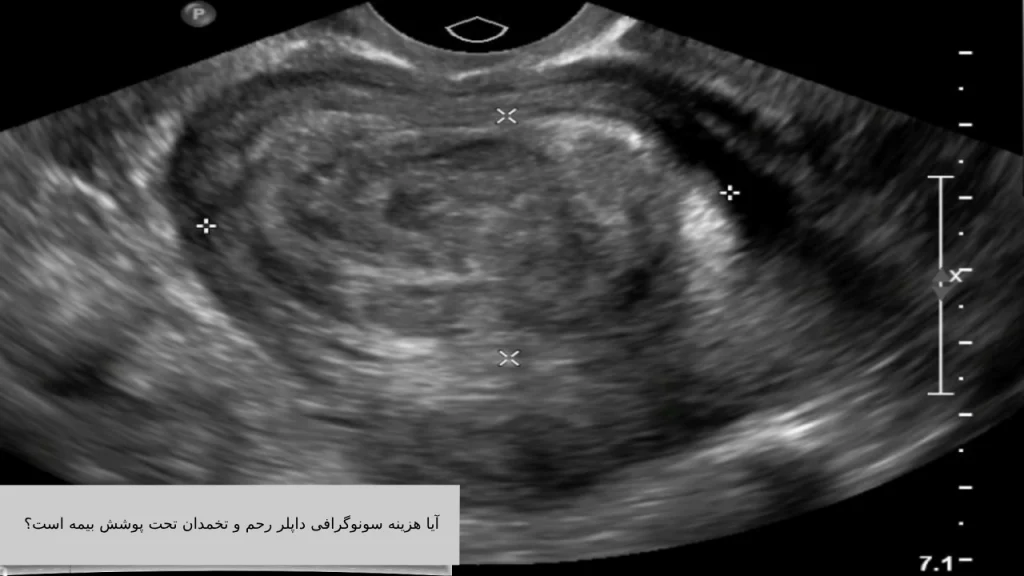

آیا هزینه سونوگرافی داپلر رحم و تخمدان تحت پوشش بیمه است؟

بله، هزینه سونوگرافی داپلر رحم و تخمدان در برخی شرایط خاص تحت پوشش بیمههای درمانی قرار میگیرد، اما این پوشش به عوامل متعددی بستگی دارد که در ادامه بهطور کامل توضیح داده شده است:

۱. بیمههای پایه (تأمین اجتماعی، سلامت، نیروهای مسلح)

اگر سونوگرافی داپلر با نسخه پزشک متخصص زنان یا پزشک معالج تجویز شده باشد و دلیل پزشکی واضح مثل بررسی کیست، فیبروم، ناباروری، درد مزمن لگنی یا خونریزیهای غیرطبیعی وجود داشته باشد، بیشتر بیمههای پایه بخشی از هزینه سونوگرافی داپلر رحم و تخمدان را پرداخت میکنند.

در این حالت، بیمار باید سونوگرافی را در مرکز طرف قرارداد با بیمه انجام دهد تا تعرفه بیمهای برای او اعمال شود.

هزینه سونوگرافی داپلر رحم و تخمدان در صورت داشتن نسخه پزشک و انجام در مراکز طرف قرارداد، تحت پوشش بیمه قرار میگیرد و میتواند بخش زیادی از هزینه را کاهش دهد. اگر بیمه تکمیلی هم داشته باشید، ممکن است هزینه سونوگرافی داپلر رحم و تخمدان نهایی برای شما نزدیک به صفر شود. بنابراین بهتر است پیش از انجام این سونوگرافی، با مرکز تصویربرداری و شرکت بیمه خود هماهنگ کنید تا از جزئیات پوشش و فرآیند استفاده از بیمه مطلع شوید.